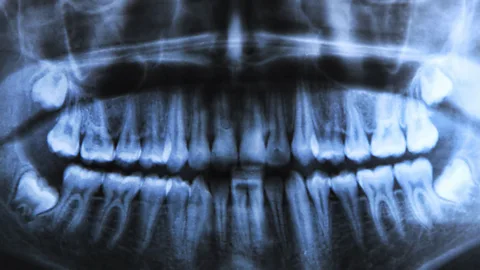

Holtorf’s device is the eyeCAD-connect system – a bit of augmented reality software developed by his firm, iDENT, that runs on a pair of smart glasses built by technology firm Epson. When Holtorf dons the glasses during a dental examination, he still sees his patient’s mouth – but superimposed over that, the glasses show real-time data coming in from his dental scanner. Once the scan is complete, Holtorf can send the data off to the lab, where technicians create a virtual model and design whatever crown or cap the patient needs.

In the past, when a dentist was scanning a patient’s teeth, they used the camera with one hand while they focused their attention on a nearby screen – much like during an ultrasound. But with the glasses, says Holtorf, the dentist can scan while looking directly at the patient, and the scans show up instantly on the augmented reality glasses. “So we avoid looking to the monitor while we’re scanning, and we don’t lose contact with the patient, and for me, that’s the idea,” he says.